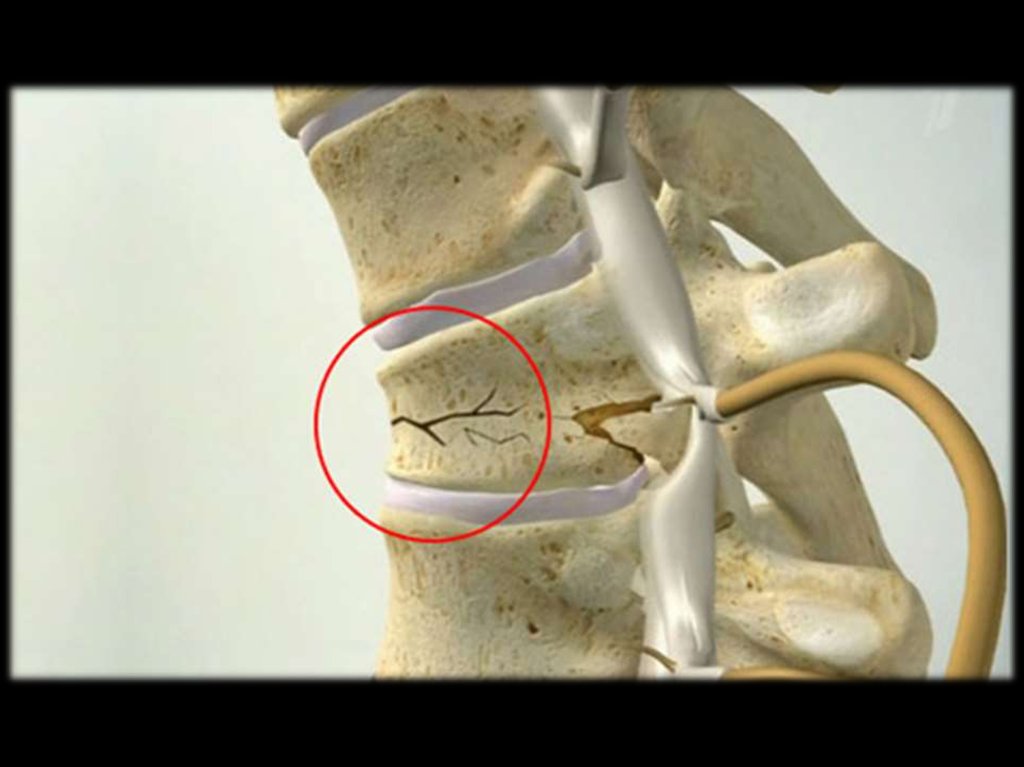

13. Клинические проявления остеопороза – признаки состоявшихся переломов

Переломы позвонков

(клинические и рентгенологические)

Острые или хронические боли в спине

или

пояснице

(неспецифический

признак)

Снижением роста (на 2 см за год или

на 4 см и более за жизнь)

Увеличение грудного кифоза

Виды деформации тел позвонков:

передняя клиновидная;

задняя клиновидная;

двояковогнутая деформация (по типу

“рыбьих”);

компрессионная деформация;

сочетанная.